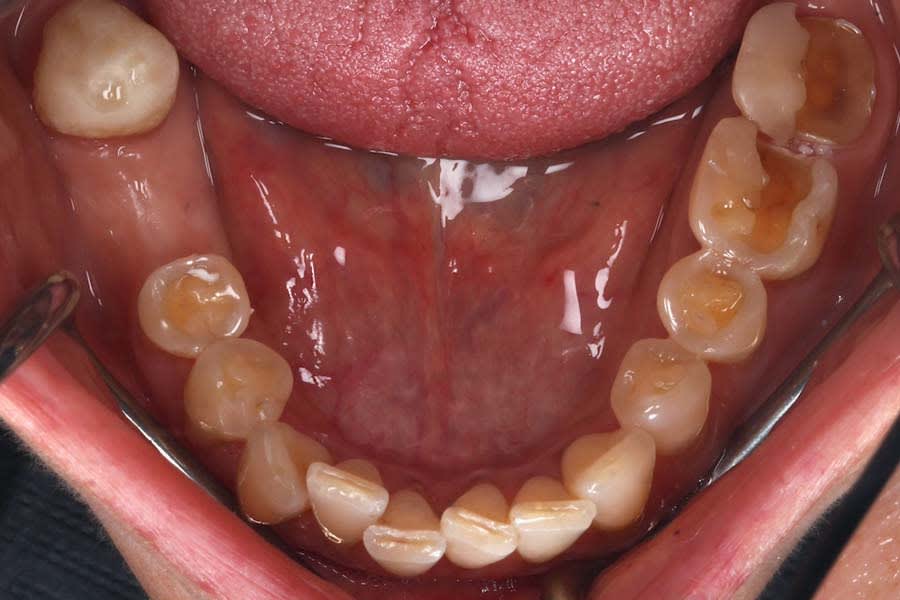

A 47-year-old female patient presented to the prosthodontics clinic at the University of Pennsylvania School of Dental Medicine with severe dental wear. Her chief complaint was that she didn’t like the appearance of her “front teeth” and was very concerned about her teeth “breaking apart” (Figure 1 and Figure 2). She reported noticing metal exposure on the existing fixed dental prosthesis (FDP) at Nos. 8 through 10 and progressive tooth wear. Her condition was causing her significant anxiety, which had worsened during a recent period of emotional stress accompanied by increased clenching. A recent tooth chipping incident with associated hypersensitivity of tooth No. 18 prompted her to seek definitive care.

Intraoral and extraoral photographs and digital scans were obtained. Bite registration was taken in centric relation, along with three additional registrations at 1 mm, 1.5 mm, and 2 mm increased OVD using a leaf gauge. Medical and dietary history revealed mild gastric reflux and habitual tea consumption. Clinical examination identified multifactorial wear, with signs of intrinsic and extrinsic erosion, attrition, and abrasion (Figure 3 and Figure 4). There was significant tooth structure loss and partial dentoalveolar compensation. The gingival phenotype was thin, with RT1 recession defects at multiple sites.27

No osseous pathology was noted on radiographic examination. All teeth yielded a positive response to thermal and electric pulp testing. Based on the history and clinical examination, the diagnosis was generalized moderate tooth surface loss due to a combination of attrition, erosion, and abrasion; partial edentulism; loss of OVD; and esthetic concerns. The patient desired a minimally invasive, esthetic, and durable treatment option.